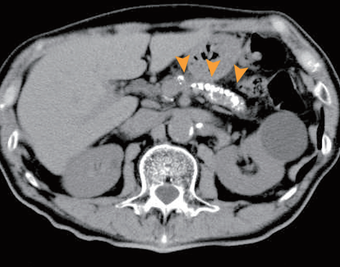

【進行した慢性膵炎、膵石症】

膵臓全体に膵石が多発している。